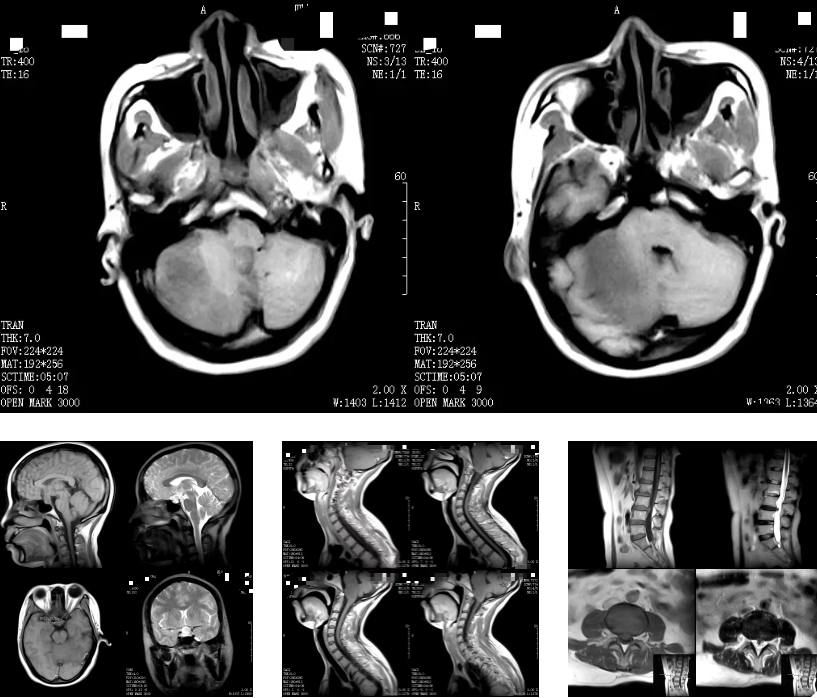

何军主任以深厚的医学造诣和前瞻性视野,从 MRI 的基本原理讲起,深入浅出地剖析了磁共振成像的奥秘,检查方法,各类适应症,禁忌症以及最新技术应用等。从理论要点到临床应用,从经典案例到前沿技术,无一不娓娓道来,深刻阐述了 MRI 技术对于现代临床工作的重大意义。他强调:「MRI 以其无创、多参数、高分辨率等独特优势,在中枢神经系统、心血管系统、骨关节及肌肉系统、颈部、腹部、盆腔等病变的诊断中展现出无可替代的价值,希望参与本次培训的医师们能够从中受益,学以致用。」